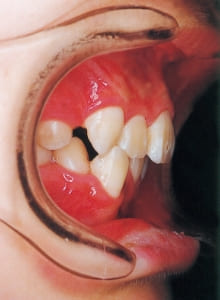

3 Initial Visit 2-11-’88

4 Initial Visit 2-11-’88

The Class II condition is pronounced, with a significant overjet of 12.5 mm(3). Although the teeth size are large, crowding is relatively mild. The maxillofacial structure has good depth and a robust bone framework(5). The mandible itself is solid , robust gonial angle, but there is significant anterior-posterior displacement relative to the maxilla(ANB 10.0°). While there is no confirmed history of thumb-sucking or similar habits, the lower lip is already pushing up against the maxillary incisors. The cause of this condition is unknown.